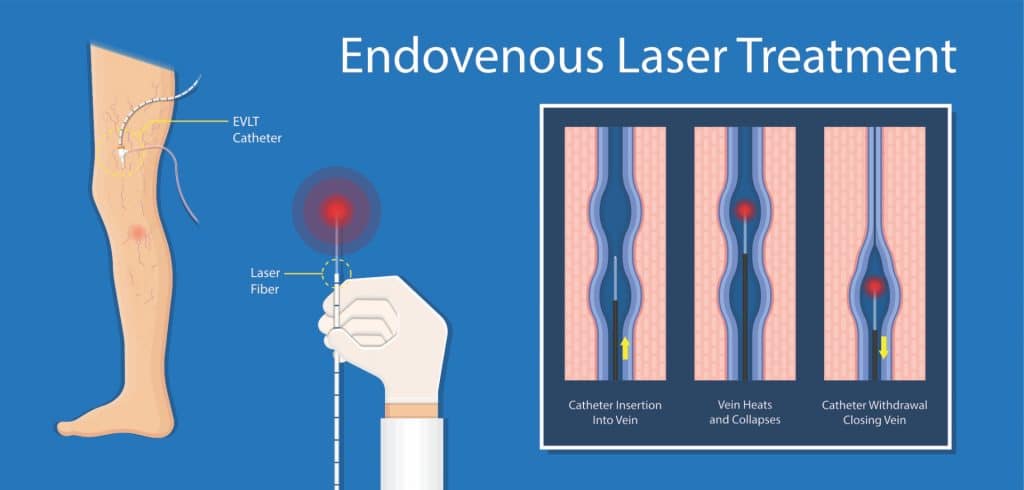

Overview

Package includes:

Days in hospital : 7 to 8 Days (For patient and one attendant)

Days in hotel : 14 Days (For patient and one attendant)

Room type in hospital : Shared

Room type in hotel : Private

Hotel category: Standard

Value added benefits of the Endo-Vascular Laser Therapy EVLT:

Ø Doctor consultation charges

Ø Lab tests and diagnostic charges

Ø Room charges inside hospital during the procedure

Ø Surgeon Fee

Ø Nursing charges

Ø Hospital surgery suite charges

Ø Anesthesia charges

Ø Routine medicines and routine consumables (bandages, dressings etc.)

Ø Food and Beverages inside hospital stay for patient and one attendant.

Extra benefits:

ü Interpreter

ü Visa assistance

Ø Site tourism of the city

Ø Follow up with the doctor

Ø Airport pick up and drop

Ø Free online consultation with the doctor

Ø Priority appointments with the doctor

Ø Room upgrade from sharing to private